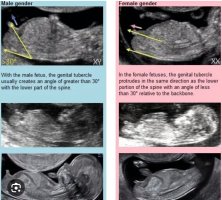

Jeg tipper gutt, fordi strekene peker skrått i forhold til ryggen.Hvilket kjønn tipper dere her?11+4 i går, så fortsatt veeeldig tidlig.

Ikke noe feil med bilde her, verken navlestreng eller for smått bilde. Det ser ut som ei jente, helt enig med det

Det er for tidlig å si noe om kjønn dessverre, alle ser ut som jenter. I noen få tilfeller kan man kanskje se gutt en dag eller to før uke 12 hvis det er en som er litt frempå i utvikling, men det er ikke vanlig. Jenter kan bli til gutter helt frem til 12+5 sånn egentlig. Alle vil se ut som jenter før uke 12, så det at dette ser ut som jente betyr ikke at det er det dessverre.